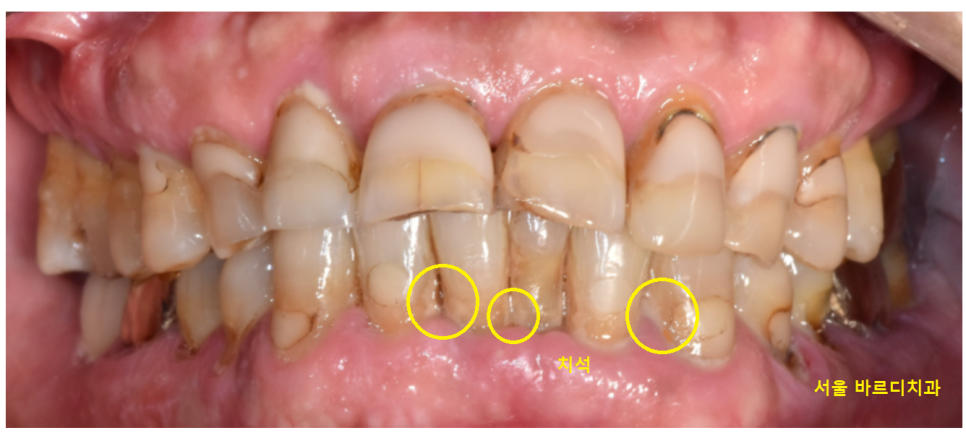

23.05.11

잇몸치료 전 잇몸입니다.

치아 뿌리 부분에 울퉁불퉁한 조각들이

붙어있죠~?

상일동역 스케일링을 1차 받고

찍은 사진임에도 큰 치석들이 남아있습니다.

일반적인 치석제거로는

뿌리쪽이 제거가 어렵기 때문에

잇몸치료가 꼭 필요한데요!!